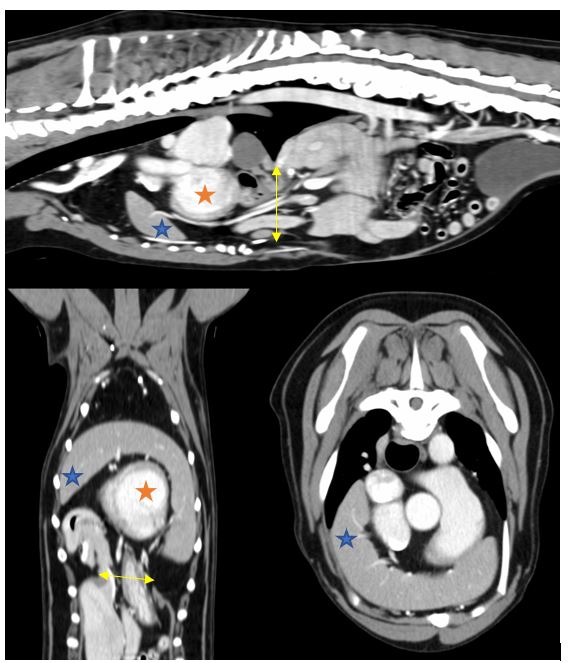

Due to the findings on the abdominal ultrasound, it was decided to perform a CT scan to further characterise the diaphragmatic defect and precisely locating all displaced viscera. On CT scan a large 4cm defect was discovered in the diaphragmatic midline slightly caudal the foreshortened and abnormally shaped sternum (Figure 2). The spleen, gall bladder, pancreas, pyloric antrum, and proximal duodenum were all herniated through this defect and likely sitting within the pericardial sac surrounding the heart ventrally, confirming a diagnosis of Congenital Peritoneopericardial Diaphragmatic Hernia (cPPDH). Although not featured highly on our differential list cPPDH is a recognised congenital defect that often involves herniation of organs into the pericardial space. Due to its nature as a congenital condition, it is often diagnosed early in a patient’s life, but, as occurred in this case, some dogs can live with a cPPDH for several years with no obvious clinical abnormalities. In this patient we believe the presenting signs (lethargy, exercise intolerance, weight loss, intermittent vomiting, and PU/PD) were due to the visceral pain or nausea caused by herniation of abdominal visceral through the diaphragmatic defect. An increase in ALT is a common laboratory finding in both cats and dogs with cPPDH, supposedly caused by trauma to the liver, as previously described in the literature. (Banz & Gottfried, 2010). The combination of diaphragmatic, pericardiac, body wall and sternal defects makes this a likely case of incomplete pentalogy of Cantrell (Benlloch-Gonzalez & Poncet 2015, Williams et al. 2020).

Figure 2; Three CT scan views of the thorax showing herniated viscera extending through the diaphragmatic defect (indicated by yellow arrow) into the pericardial sac. The spleen (indicated by blue star) can be seen extending around the cranial border of the heart (indicated by orange star).